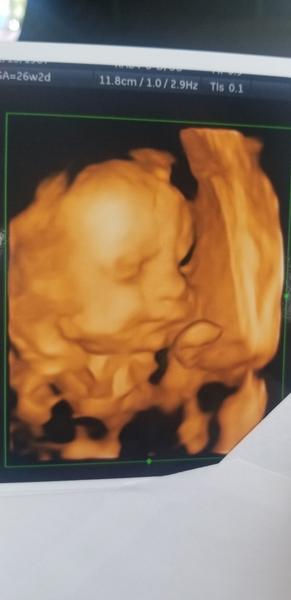

Ja mam termin 17.12 alebo 19.12 dufam ze to bude niekedy vtedy alebo pred 🙂 zatial to este nevyzera, som v 36 +4tt je otocena dole hlavou ale este je tak vyssie, nezosunula sa este, visc menej je na pol ceste :D mala som kontrolu vo stvrtok a vsetko oki 🙂 este aj fotecka sa nam podarila 🙂 uz sa moc tesim, ale aj panika ma chyta trosku z porodu a tak vsetkeho. Mate uz vsetko nakupene, pochvalte sa s kocickami a izbickami a babatkami ked budu 😊😍 fotecky su stvrtok a v 26tt 3d sono 🙂